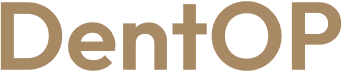

Simțea că nu mai poate mânca și zâmbi cu încredere. Lucrările vechi pe care le purta au determinat-o să facă o schimbare în viața ei. Doamna N. a ales procedura ,,Dantură Fixă în 24h pe implanturi dentare” pentru a avea un zâmbet frumos și mai ales sănătos.

În doar 24h i-au fost inserate și lucrările provizorii pe implanturi. Pacienta le-a purtat aproximativ 6 luni, iar acum a beneficiat și de lucrările finale menite să o însoțească pentru cât mai mult timp.

Suntem bucuroși că am putut să o ajutăm pe pacienta noastră dragă și că ne-a oferit încrederea ei pe parcursul procedurii.